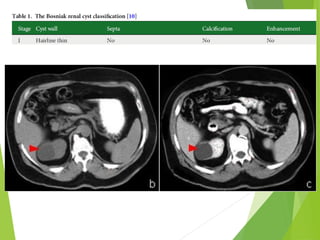

morphological

description, Stage I renal

cyst (Bosniak

Classification)

Radiographic features , CT:

Smooth cyst wall

Sharp demarcation

Homogenous Water

density (< 10-15 HU)

No significant enhancement

after IV contrast (<5HU)

Cyst wall too thin to be seen by CT

Radiographic features ,CT: Smooth cyst wall Sharp demarcation Homogenous Water density (< 10-15 HU) No significant enhancement after IV contrast (<5HU) Cyst wall too thin to be seen by CT